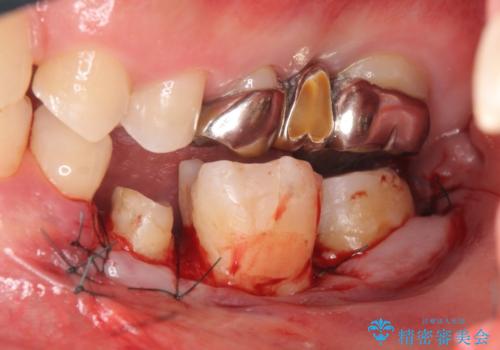

- 左下の奥歯がズキズキ痛むので診て欲しいといらっしゃった方の症例です。他院では5番目と7番目の歯を抜歯してインプラントと言われたが、出来れば歯を残したいとのことでした。

痛みの原因は6番目の虫歯であること、5番目、6番目の歯は歯茎より深い虫歯であり現状では保存が難しいことを説明した上で、歯を挺出させる部分矯正と歯茎を下げる歯周外科を行いました。

手術後歯茎の治癒を待ち、オールセラミッククラウンによる補綴を行いました。